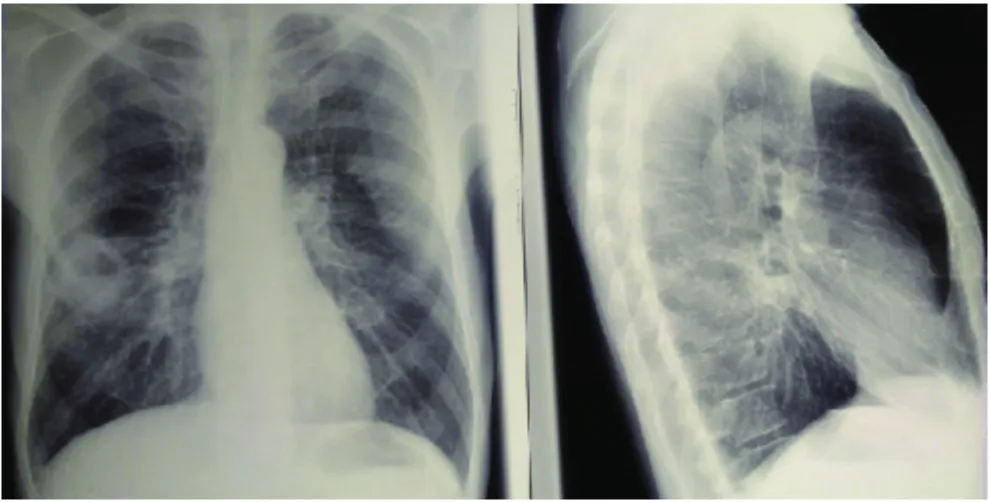

63세 남성이 10일 전부터 발생한 발열, 기침, 누런 가래 증상으로 내원하였다. 환자는 가래에서 나는 악취를 호소하였으며, 25갑년의 흡연력을 가지고 있고, 최근 4년 동안 매일 소주 1병 반씩을 마시며 술에 취해 의식을 잃은 적이 여러 번 있다고 한다. 환자의 구강 위생 상태는 좋지 않으며, 심한 치주염을 앓고 있다. 환자의 가슴 X선 사진을 참고하여 적절한 치료 방법을 결정하시오.

• 알콜 중독자가 나쁜 구강 위생 상태를 보이며 고열, 기침, 누런 가래를 보이고 있다. 만취 후 의식을 잃었다는 것은 흡인 폐렴의 가능성을 시사한다. 가슴 X선 상에서 RML에 air-fluid level, thick walled cavity가 보이므로 폐농양을 진단할 수 있다.